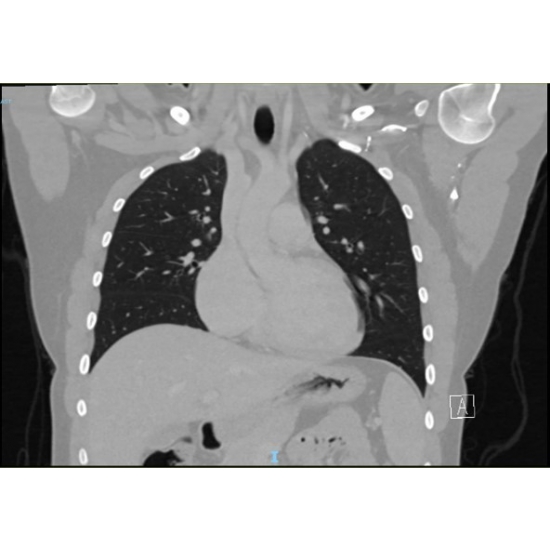

CT Head Case Photo #1 , CT Head/Neck Case Photo #2 , Brain MRI [Photo3] and CT Chest Case Photo #4 were all normal.